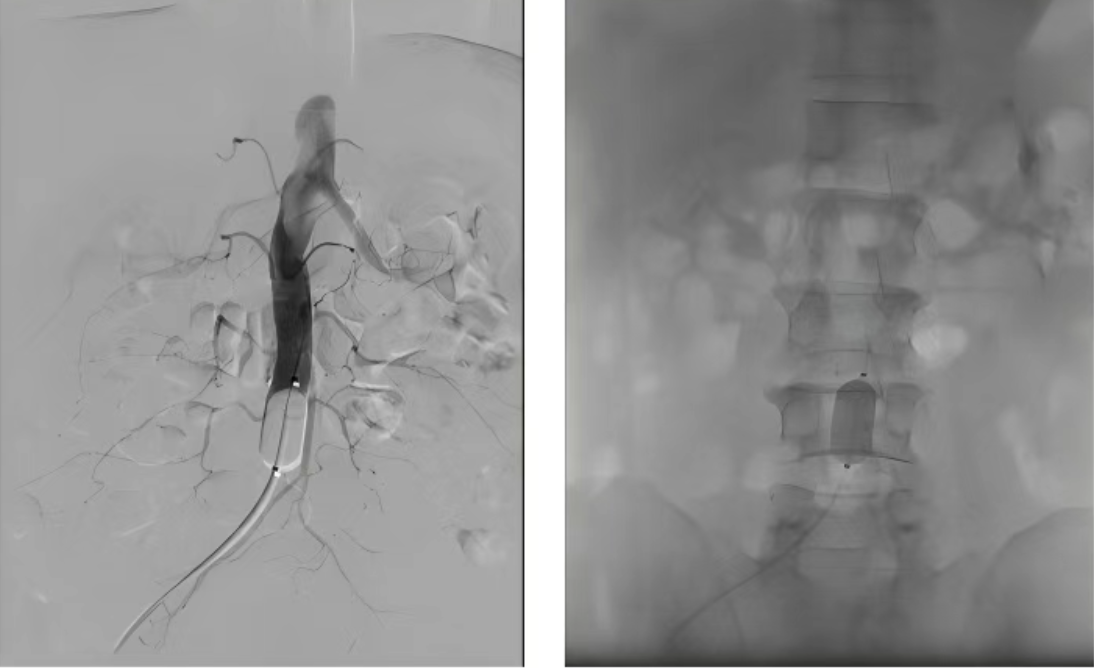

介入放射科 · 控制“水路”

肿瘤内部血管丰富,手术时易大出血,好比“装修”时先要关水阀总闸。

介入放射科团队率先行动,精准实施腹主动脉球囊阻断,暂时控制了肿瘤的主要“补给线”,为大手术清场,保证了操作空间的安全与清晰。